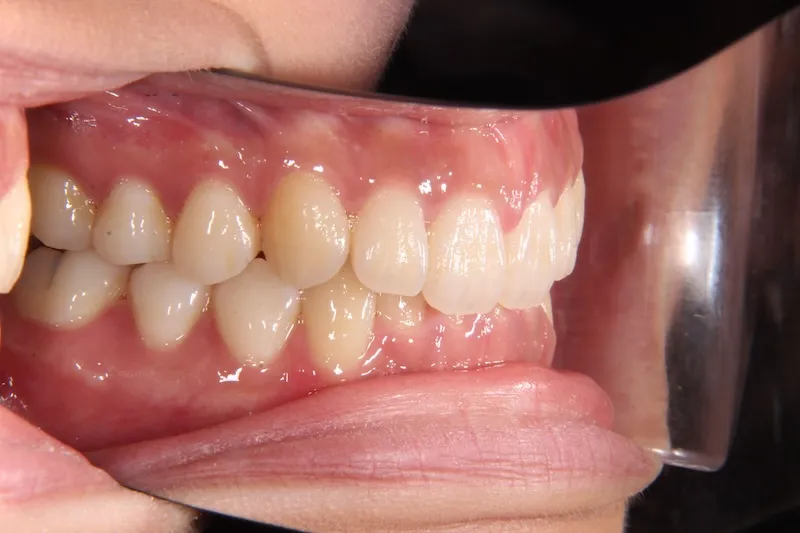

治療経過1